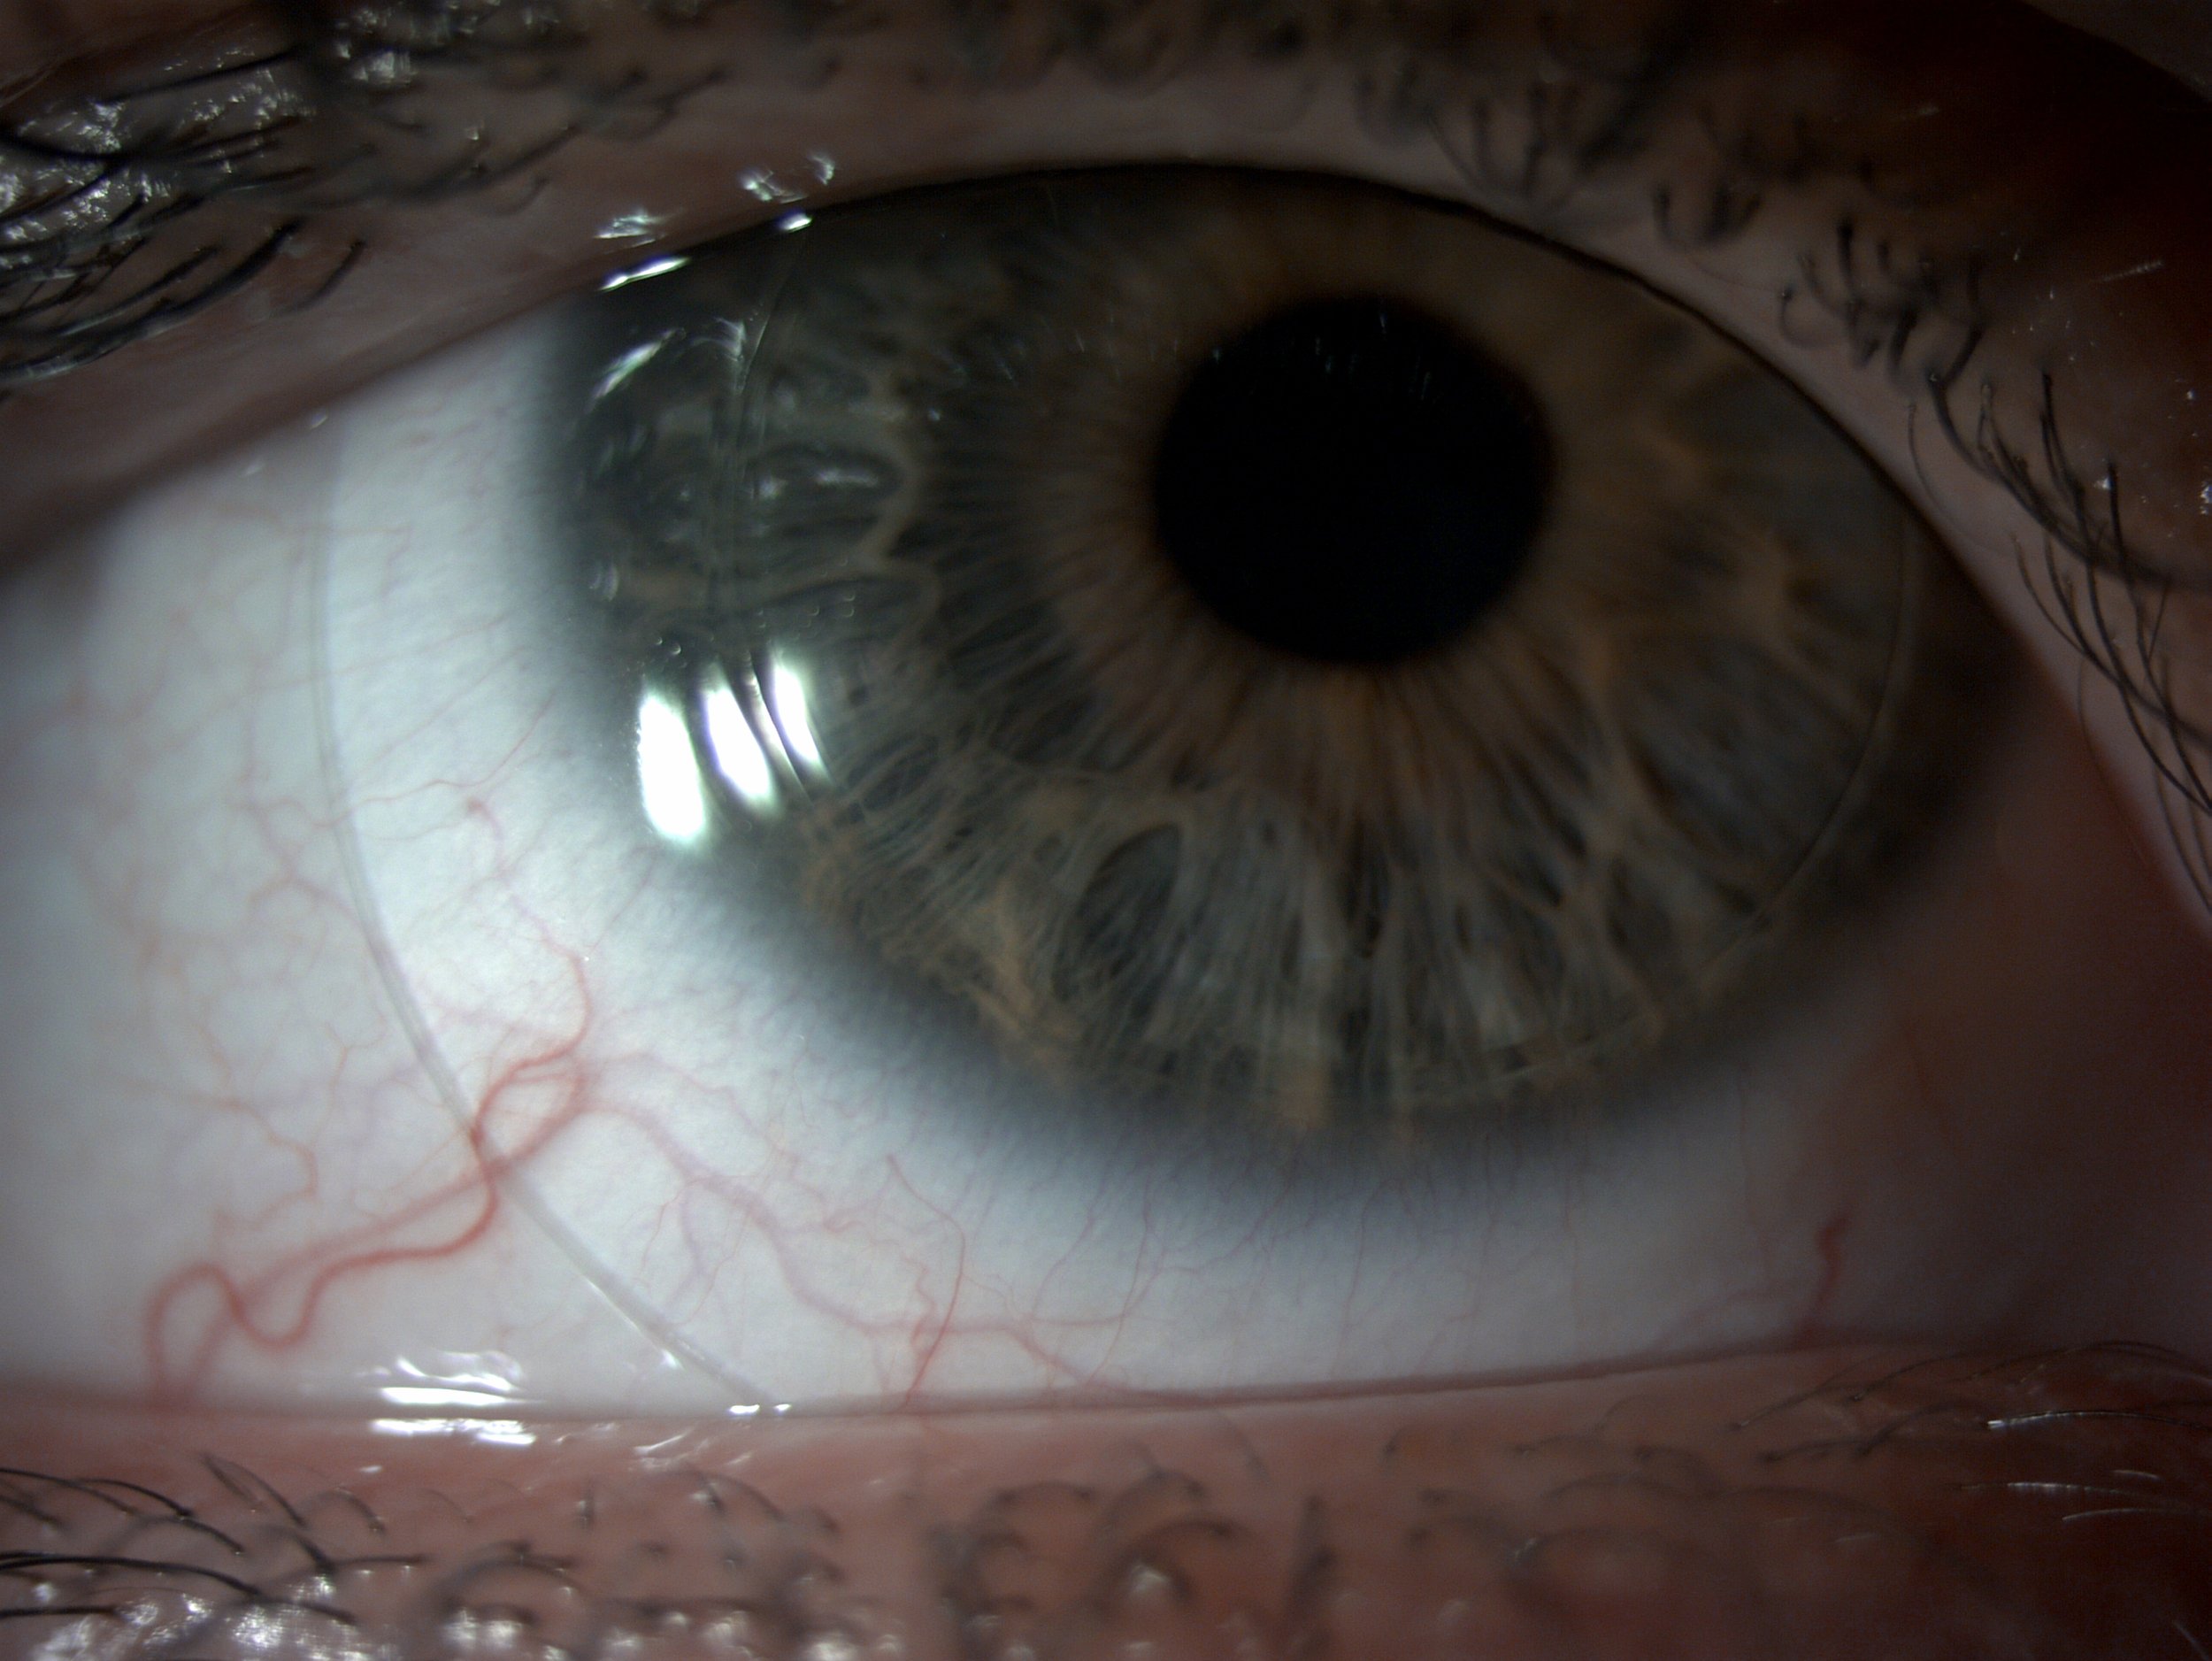

Scleral lenses are large diameter gas-permeable contact lens devices.

Rather than sitting directly on the eye like a traditional soft lens, scleral lenses only touch the sclera (the white part of the eye) and vault entirely over the cornea (the front of your eye - a clear layer of tissue that covers your iris, pupil and lens). This vault - the space between the contact lens and your cornea - is filled with fluid and creates a new, perfect focusing surface.

By vaulting over the eye with fluid, we are able to manage complicated eye conditions such as astigmatism, keratoconus, corneal transplants, severe dry eye, corneal scarring, LASIK complications and more. These lenses can be life changing.